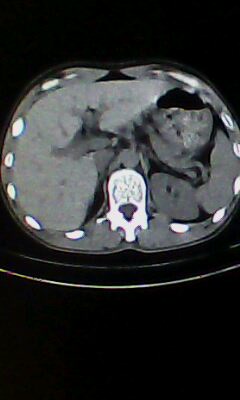

胰尾部占位?

未见明显异常。“胰尾占位”为肠管

口服造影剂是必须的

弥漫性肺气肿 但内胆管轻度扩张